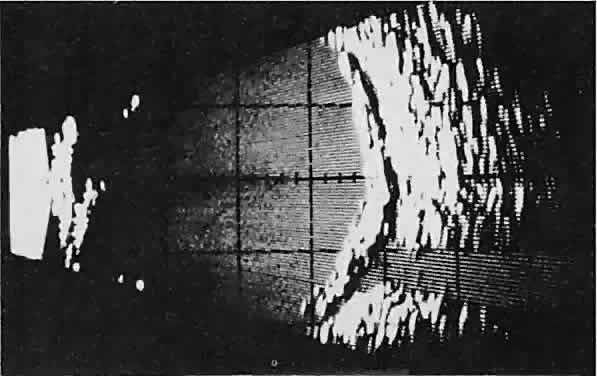

infiltrates normal tissue. Echography shows internal echoes of

low-to-medium amplitude. Because the cellular tumor absorbs acoustic

energy, the amplitude of the spikes falls off somewhat through the lesion (see Fig. 1B and C). MRI can help define the tumor's relationship to extraocular muscles (Fig. 2).  Fig. 1. A. Proptosis and downward, outward globe displacement developed over 2 days

in a 3-year-old girl. A homogeneous mass fills the superomedial orbit. B. Contact B-scanning shows a relatively well-circumscribed mass with uniform

internal echoes. C. Contact A-scanning shows the internal reflectivity to be of low to medium

amplitude, consistent with a sarcomatous lesion. Biopsy results confirmed

the diagnosis of rhabdomyosarcoma. Fig. 1. A. Proptosis and downward, outward globe displacement developed over 2 days

in a 3-year-old girl. A homogeneous mass fills the superomedial orbit. B. Contact B-scanning shows a relatively well-circumscribed mass with uniform

internal echoes. C. Contact A-scanning shows the internal reflectivity to be of low to medium

amplitude, consistent with a sarcomatous lesion. Biopsy results confirmed

the diagnosis of rhabdomyosarcoma.